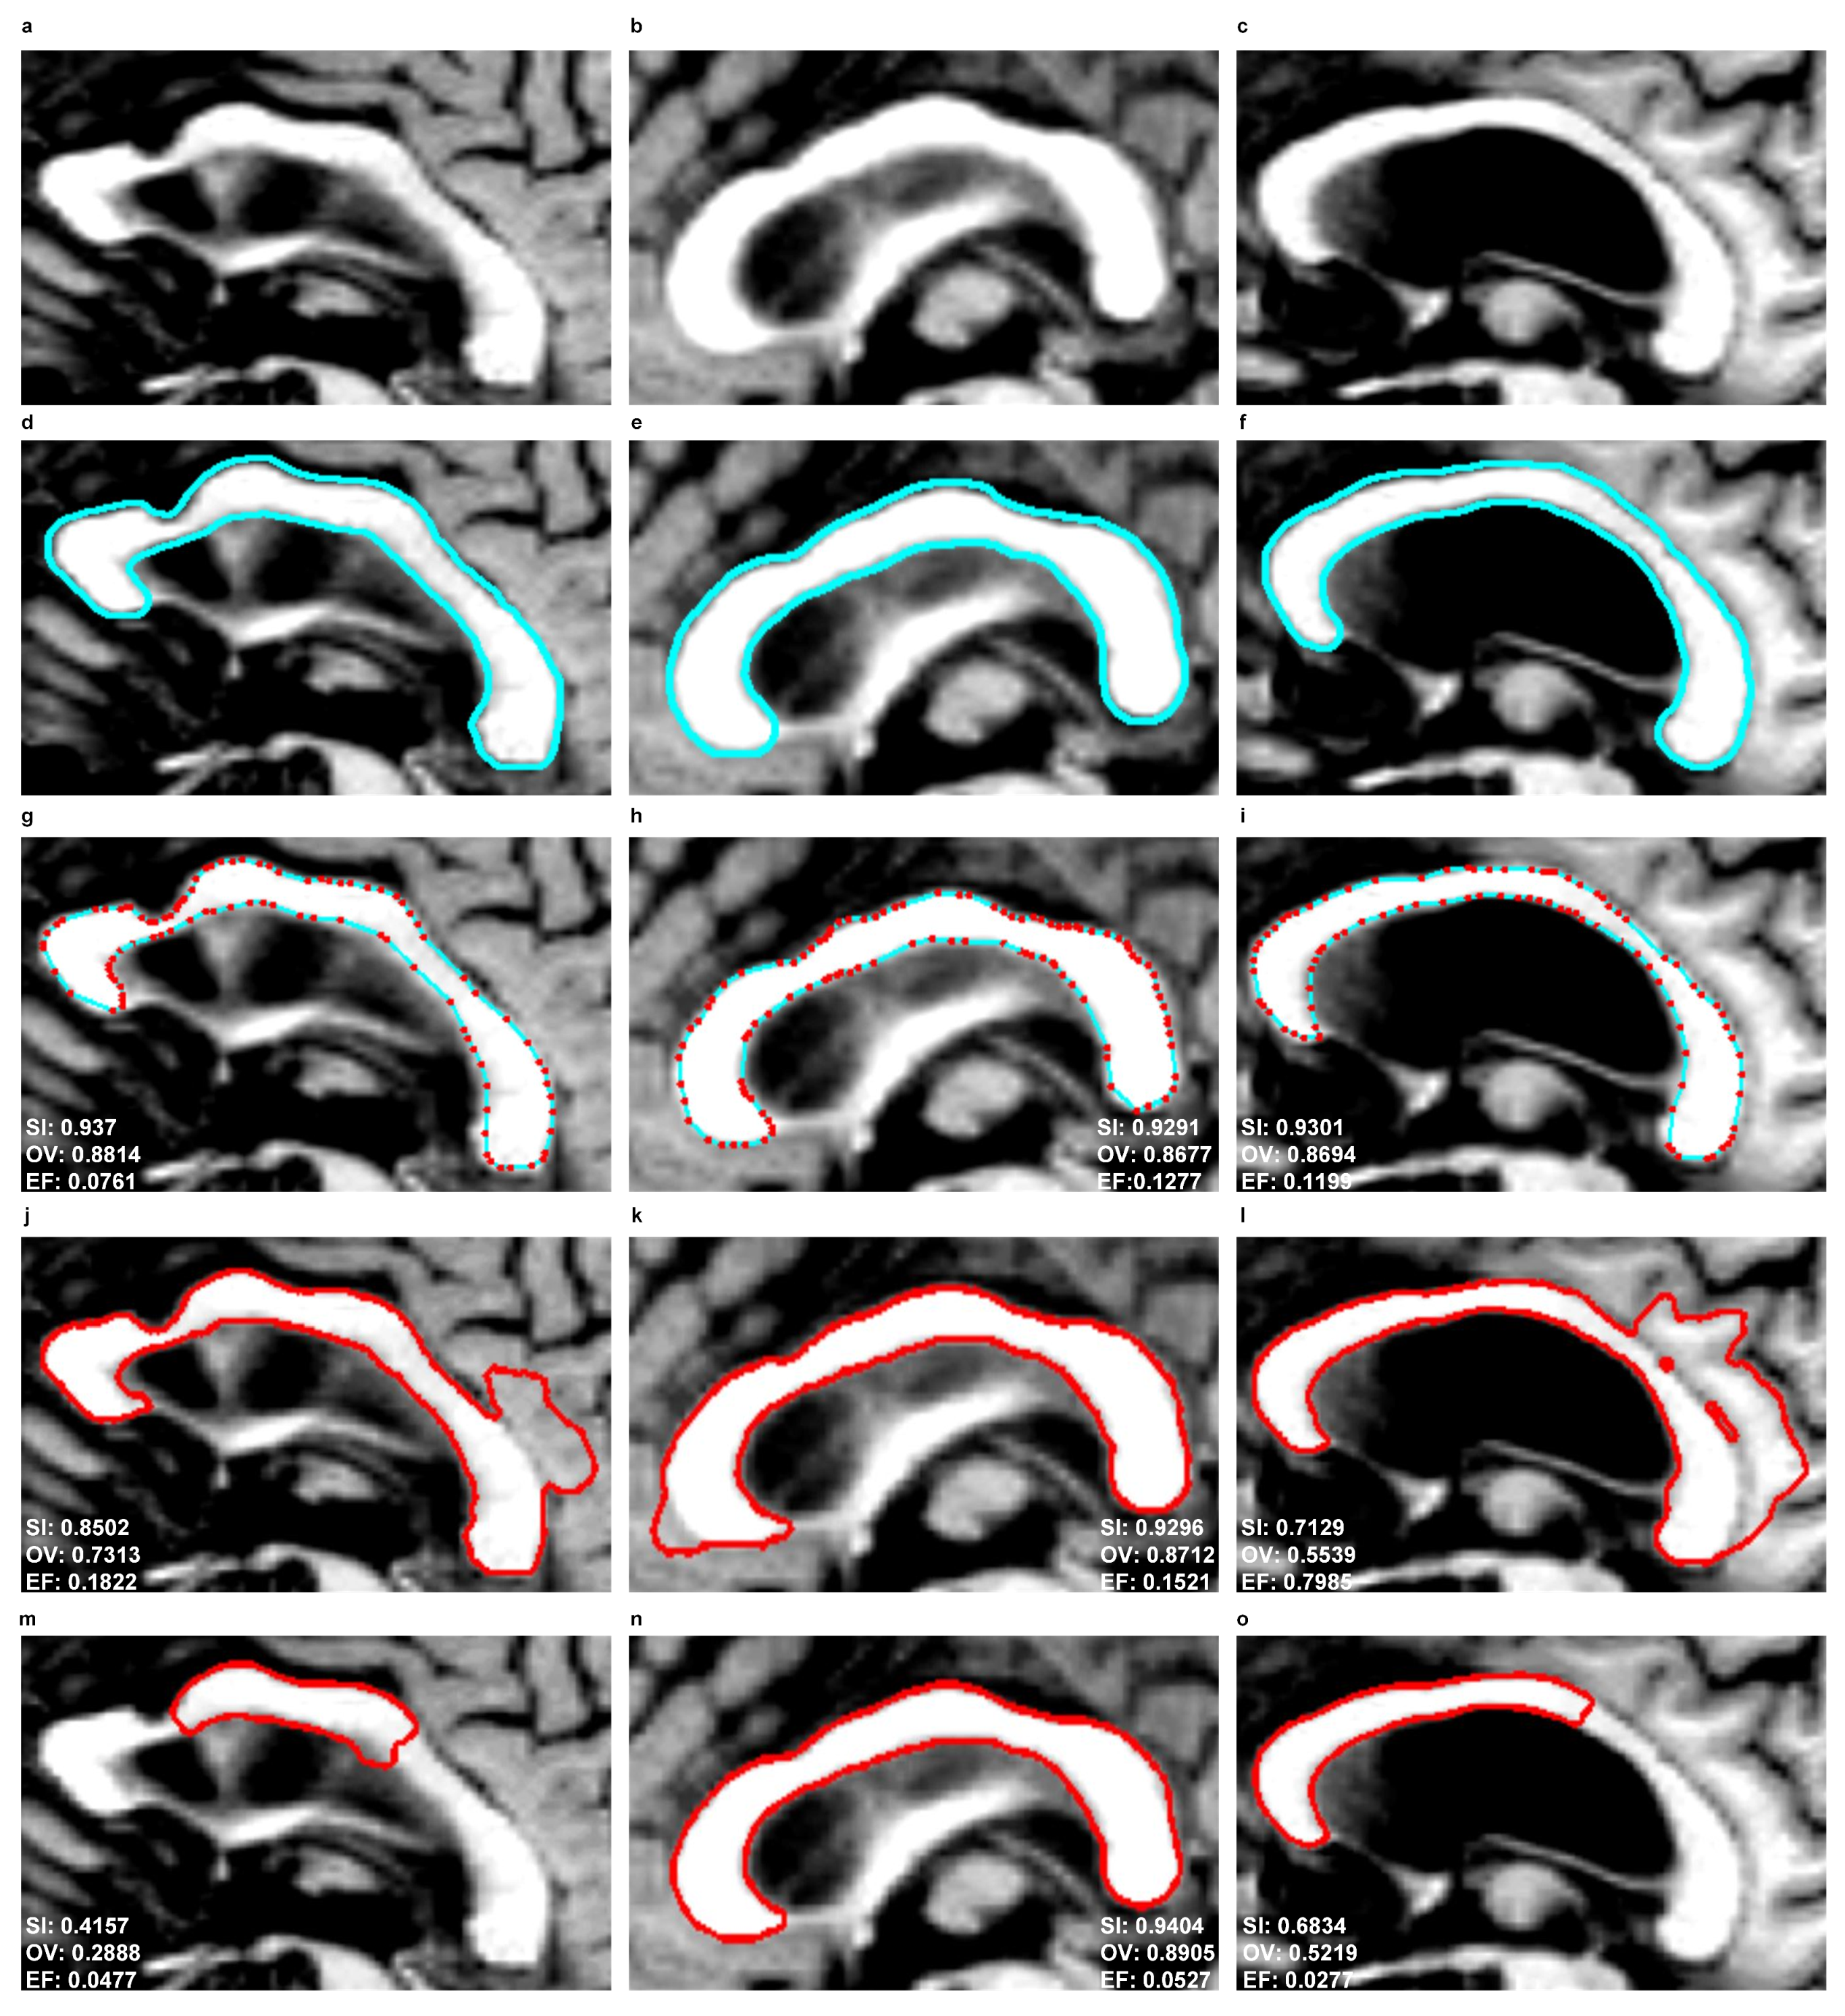

Figure 10 and Figure 11 show the segmentation results produced by the EM, SBGFRLS and DRLSE models as well as the contours manually traced by an experienced physician ( E 1 ). In the EM model, the CC contours obtained in the previous or subsequent slices of MR images can be used for initiations in the next or previous slices.

As a result of the experiments carried out, the EM model produced significantly better results of the mean SI (92%) and OV (85%) indices than SBGFRLS (SI = 82%, OV =72%) and DRLSE (SI = 73%, OV = 67%). Segmenting the CC using the DRLSE model may produce the greatest underestimation, as proven by the lowest minimum values of the S I and O V indices, which, for the DRLSE, amount to 41% and 28%, as also shown in examples from Figure 11m,o. The DRLSE and SBGFRLS models allow high segmentation results to be obtained for single CC slices, which has also been demonstrated in source articles [13,14]. However, if the entire set of CC slices is analysed as necessary to obtain an accurate 3D CC reconstruction, wrong segmentations (under- or over-segmentations) are produced for some images.

The average mean value of the E F indice is the lowest for the DRLSE model and amounts to 9%. The EM and SBGFRLS models produced mean values of the EF indice amounting to 12% and 36% respectively, so if the SBGFRLS model is used, a very high over-segmentationmay occur.

Symmetry 10 00589 g010

Figure 11. Comparison of corpus callosum segmentation results for example MR images taken from three sets from the MIRIAD database. First column: ‘miriad_234_AD_M_03_MR_2’, second column: ‘miriad_244_AD_F_01_MR_2’, third column: ‘miriad_257_AD_F_05_MR_1’. First row: ROIs from MR images of the corpus callosum based on the sagittal plane, Second row: contours traced by a physician ( E 1 ), Third row: contours produced by the EM model, Fourth row: use of the SBGFRLS model, Fifth row: the DRLSE model.

Symmetry 10 00589 g011